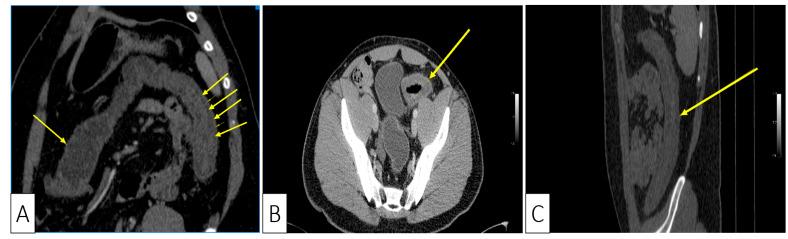

Gut microbiota plays an important role in the wellbeing of the host through different interactions between microflora constituents. In certain instances, may pullulate, causing infection with associated colitis that may vary in terms of severity from mild disease to severe colitis, with increased associated mortality due to its complications. However, there are few literature data regarding the association between and ischemic colitis. We report the case of a 30-year-old male patient, overweight, with impending dehydration, who presented with hematochezia and colicky abdominal pain, with positive fecal tests for the detection of infection and endoscopic appearance suggesting ischemic colitis in the sigmoid and left colon, confirmed by computed tomography and histology. The patient was treated with oral Vancomycin, with resolution of symptoms, and was reevaluated through colonoscopy eight weeks after discharge, with endoscopic mucosal normalization and histological scarring process on biopsy samples. We report one of the few cases in the literature of ischemic colitis associated with infection, with resolution of clinical, endoscopic, and histologic changes after specific treatment with oral Vancomycin suggesting a possible association between the two diseases. We also review the existing literature data regarding this comorbid association.

肠道微生物群通过微生物组成部分之间的不同相互作用对宿主的健康起着重要作用。在某些情况下,可能会过度生长,导致感染相关结肠炎,其严重程度从轻度疾病到重度结肠炎不等,并因并发症而导致死亡率增加。然而,关于 和缺血性结肠炎之间的关联的文献数据很少。我们报告了一例 30 岁男性患者,超重,有脱水的危险,出现血便和痉挛性腹痛,粪便检测呈阳性,提示感染 和内镜表现提示乙状结肠和左结肠缺血性结肠炎,计算机断层扫描和组织学证实。患者接受口服万古霉素治疗,症状缓解,出院后 8 周通过结肠镜检查重新评估,内镜黏膜正常化和活检样本的组织瘢痕过程。我们报告了文献中少数几例与 感染相关的缺血性结肠炎病例之一,经口服万古霉素特异性治疗后临床、内镜和组织学改变得到缓解,提示这两种疾病之间可能存在关联。我们还回顾了关于这种合并症关联的现有文献数据。